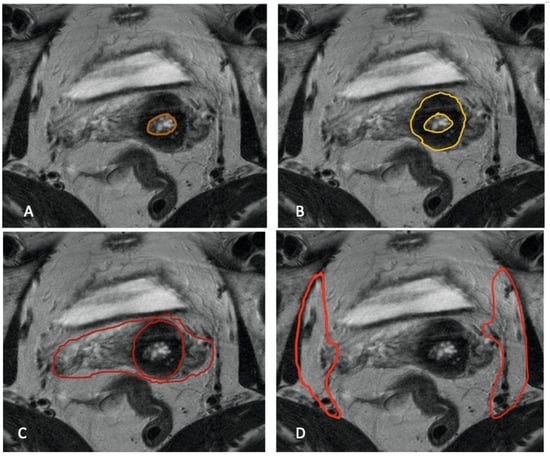

3.1. Stromal Invasion

3.2. Parametrial Invasion

3.3. Vaginal Involvement

3.4. Pelvic Side Wall